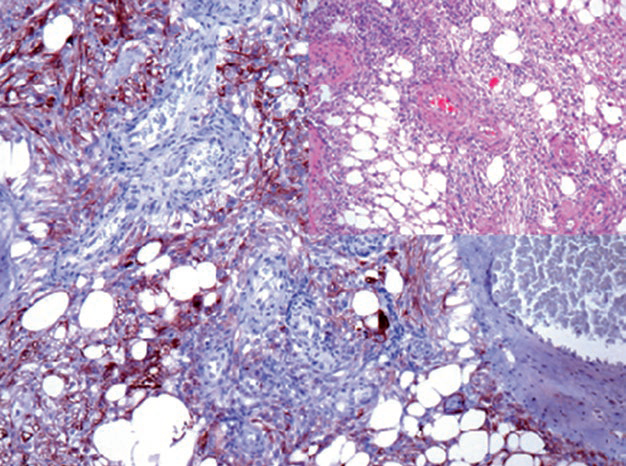

图2. 胚胎12周的肾脏,Pax-8在肾脏集合系统及肾盂处尿路上皮阳性表达。